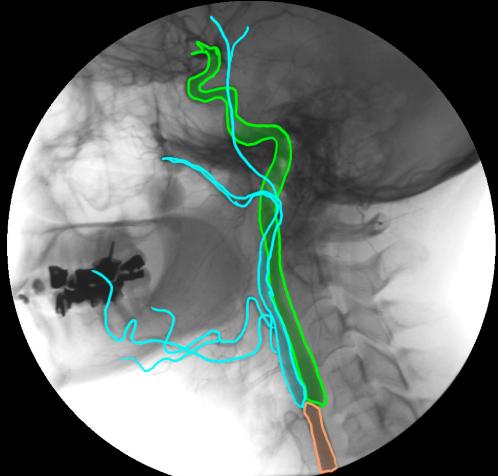

This is a lateral angiogram of the carotid artery in a normal patient. The common carotid is shown in orange, the internal carotid in green, and the external carotid and some of its branches in blue.